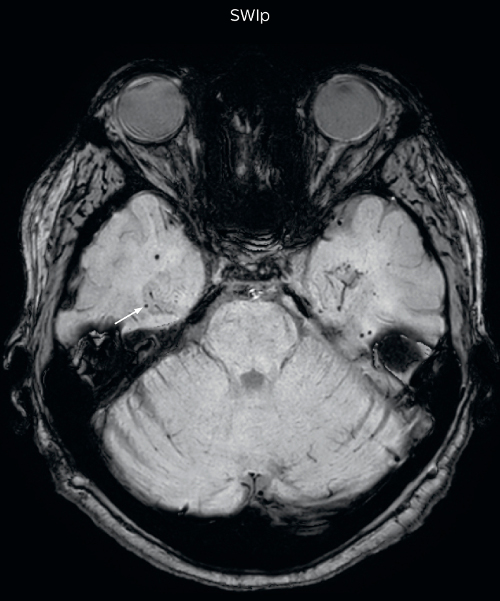

Neuroradiologist Joshua Nickerson, MD, discusses their findings in comparing SWIp versus T2* weighted imaging in different types of patients.

The SWIp sequence offers high resolution 3D susceptibility weighted brain imaging, which helps to visualize deoxygenated blood or calcium deposits. In combination with other clinical information, it may help in the diagnosis of various neurological pathologies

“With SWIp we are basically looking for blood byproducts. It is a sensitive method for visualizing small lesions containing deoxygenated blood. In our comparison, SWIp images are vastly better than gradient echo imaging, there’s no question of that anymore.” “We find the SWIp images very useful in three areas in particular. In patients with a history of hypertension, it offers clear visualization of hemosiderin deposition from hypertensive hemorrhages. We certainly see a greater number of foci of hemosiderin deposition on the SWIp images than on the T2* gradient echo images. In addition, it also helps us visualize amyloid depositions in patients with amyloid angiopathy.” Dr. Nickerson mentions trauma patients are the third large area where SWIp is useful. “We benefit from SWIp in trauma patients, certainly in cases with diffuse axonal injury and shearing injuries. Our study shows that SWIp usually provides us better visualization,” he says. “Apart from these three, SWIp also helps us to beautifully depict the normal venous anatomy in patients with venous outflow issues or vascular congestion. In some cases, we have seen downstream effects of arterial problems. And in patients with vascular malformations we have seen deposition of blood products associated with those.”

“We switched over entirely. SWIp is now included in all our routine brain exams. We developed two different SWIp sequences: a high spatial resolution (0.5 x 0.5 mm) version that takes 5.5 minutes and our fast SWIp that takes just three minutes. Only in patients that are moving tremendously we occasionally still acquire a gradient echo sequence.” “For us, SWIp use has resulted in more diagnostic confidence when small lesions, such as small shear injuries, vascular malformations, or minute amounts of calcification, need to be detected,” says Dr. Nickerson. “Our physicians greatly value the SWIp images. When we get patients transferred from other facilities with SWIp missing from their exam, we have several neurologists and neurosurgeons who order a new MRI exam because they want to see the SWIp images.”

Gradient echo imaging and SWIp are compared in a patient with radiation-induced foci of hemosiderin deposition. A greater number of small foci is seen on the SWIp image. Ingenia 3.0T